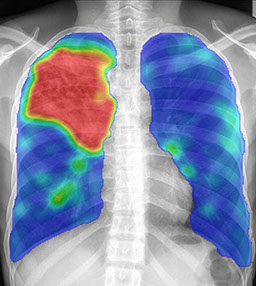

A unique innovation Delft offers is the Computer-Aided Detection for Tuberculosis software (CAD4TB). CAD4TB automatically analyses a digital chest image in less than 1 minute and scores it between 0 - 100 on abnormalities consistent with TB. Additionally, a ‘heat map’ of the lungs is generated to indicate the abnormal areas (Figure 1).

The image above shows the result from a normal digital X-Ray and then the scanning of the Delft CAD4TB software. the large RED mass shows higher levels of  infection for TB.

Figure 1

The following artificial has been copied by permission from Delft CAD4TB.